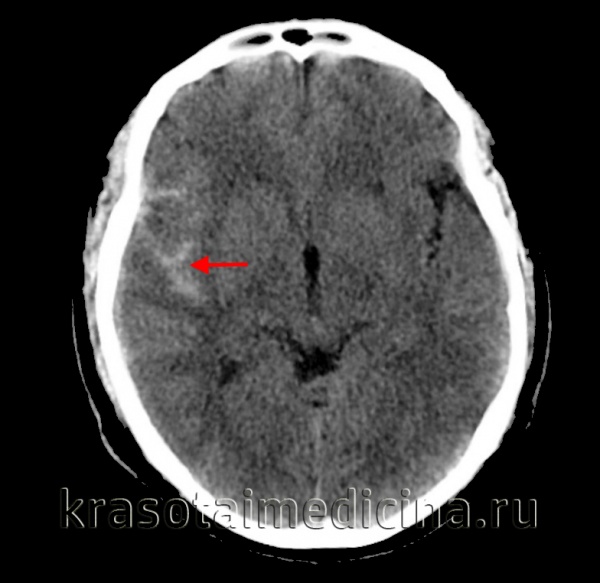

(а) КТ, аксиальный срез: в бороздах, левой сильвиевой щели, обводной цистерне, а также в межполушарной борозде определяется гиперденсное субарахноидальное кровоизлияние.

(б) Бесконтрастная КТ, аксиальный срез: небольшое скопление гиперденсной жидкости вдоль левой средней лобной борозды, представляющей собой травматическое субарахноидальное кровоизлияние.